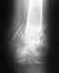

сращение перелома плеча со смещением

снимки другаяпроэкция